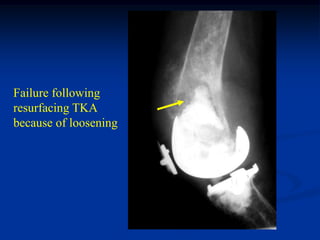

71 year female with Ollier’s left lower extremity

Lateral view of knee

Failure following

resurfacing TKA

because of loosening

Post op x-ray with constrained

TKA